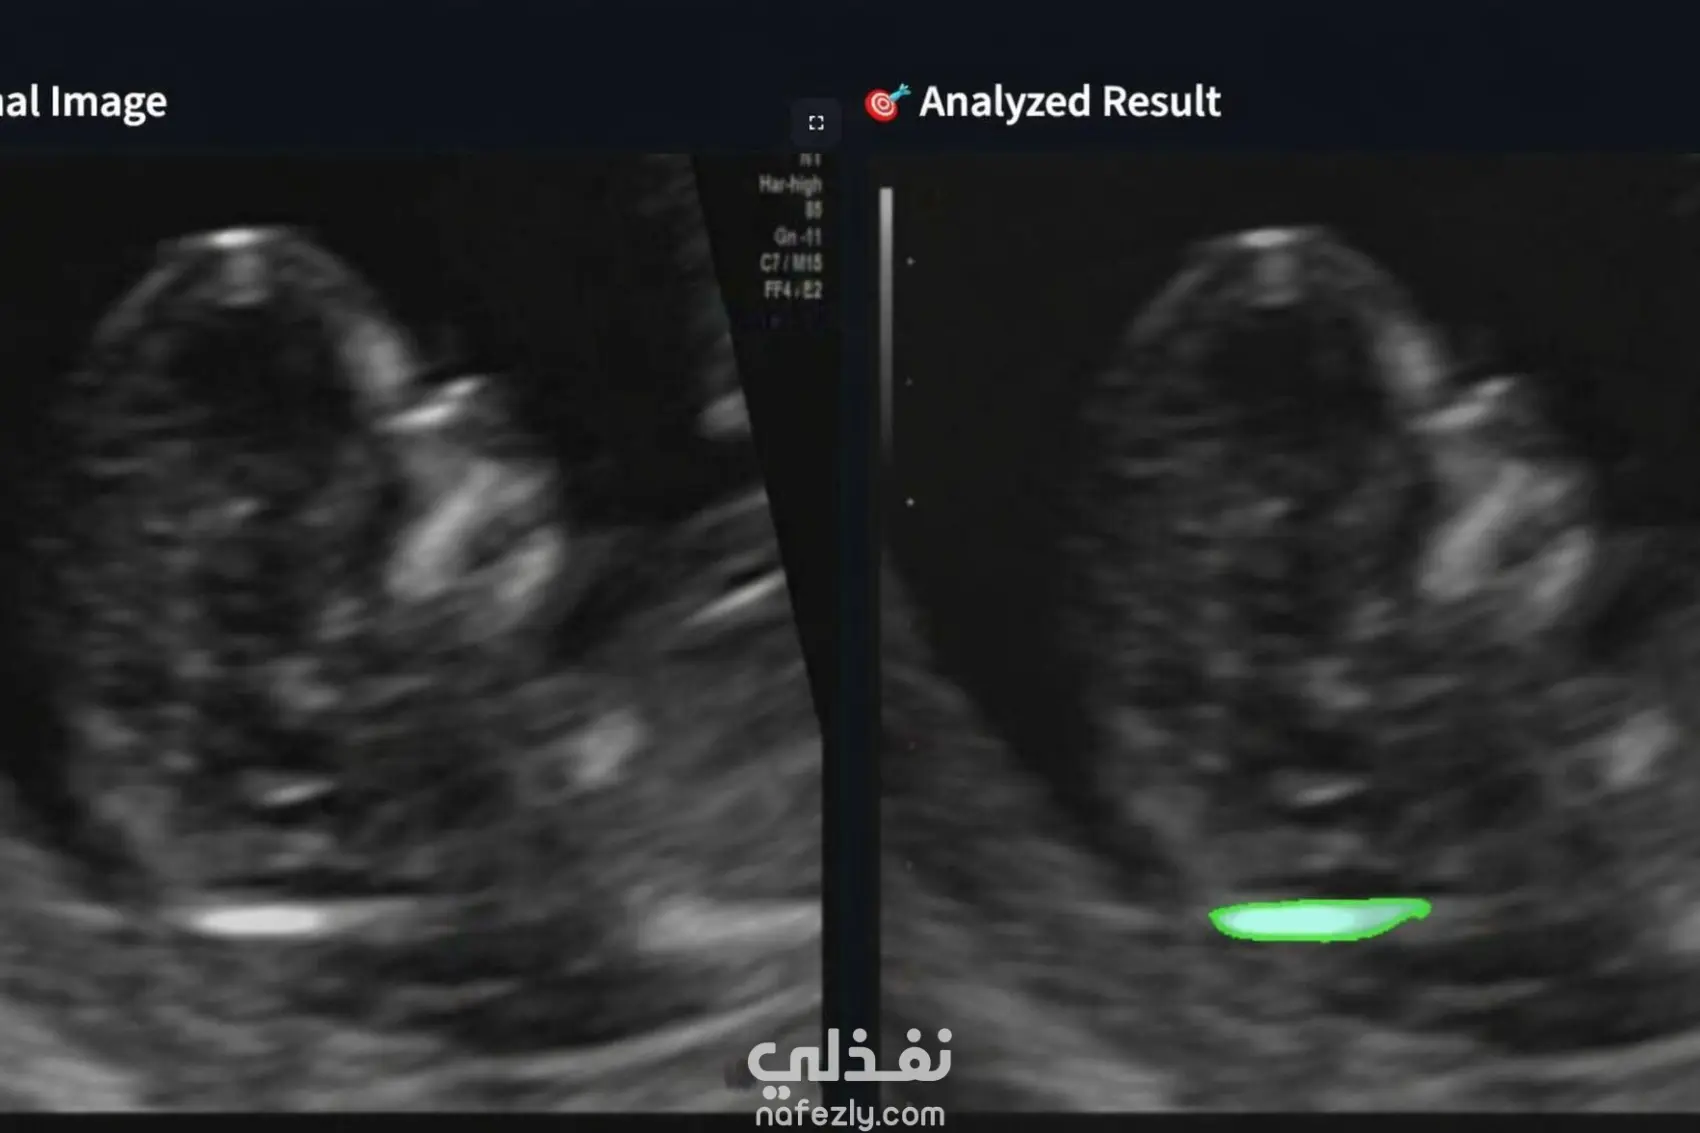

قمت بتطوير نظام يعتمد على الذكاء الاصطناعي لأتمتة قياس NT (Nuchal Translucency) في صور الأشعة بالموجات فوق الصوتية. يقوم النموذج باكتشاف منطقة NT وقياس سُمكها بدقة، ثم إنشاء تقرير منظم خلال ثوانٍ. ساهم النظام في استبدال العمل اليدوي الذي كان يقوم به فنيو المعامل، مما أدى إلى تقليل الوقت وتقليل الأخطاء البشرية. تم استخدام التعلم العميق مع نموذج ResNet وطبقات مخصّصة لاستخراج السمات وتحليل الصور الطبية بدقة.